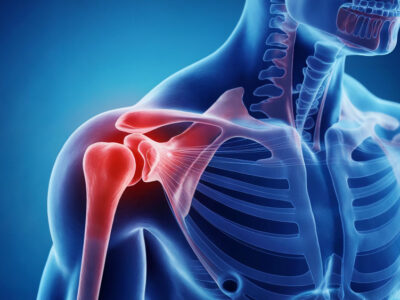

Borsite spalla: cos’è, sintomi, cause e cure efficaci

La borsite della spalla è l’infiammazione di una borsa sierosa, cioè una piccola struttura contenente liquido che ha il compito di ridurre l’attrito tra tendini, muscoli e ossa durante i movimenti dell’articolazione. Quando questa borsa si infiamma, la spalla può diventare dolorosa, rigida e difficile da muovere. Il dolore può comparire durante le attività quotidiane, …